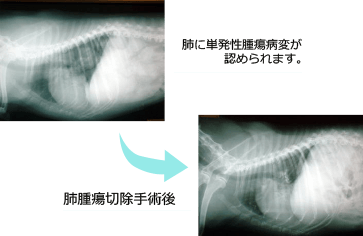

X線検査装置

X線では胸腔内・腹腔内臓器や骨・関節などに病変がないか調べることができます。